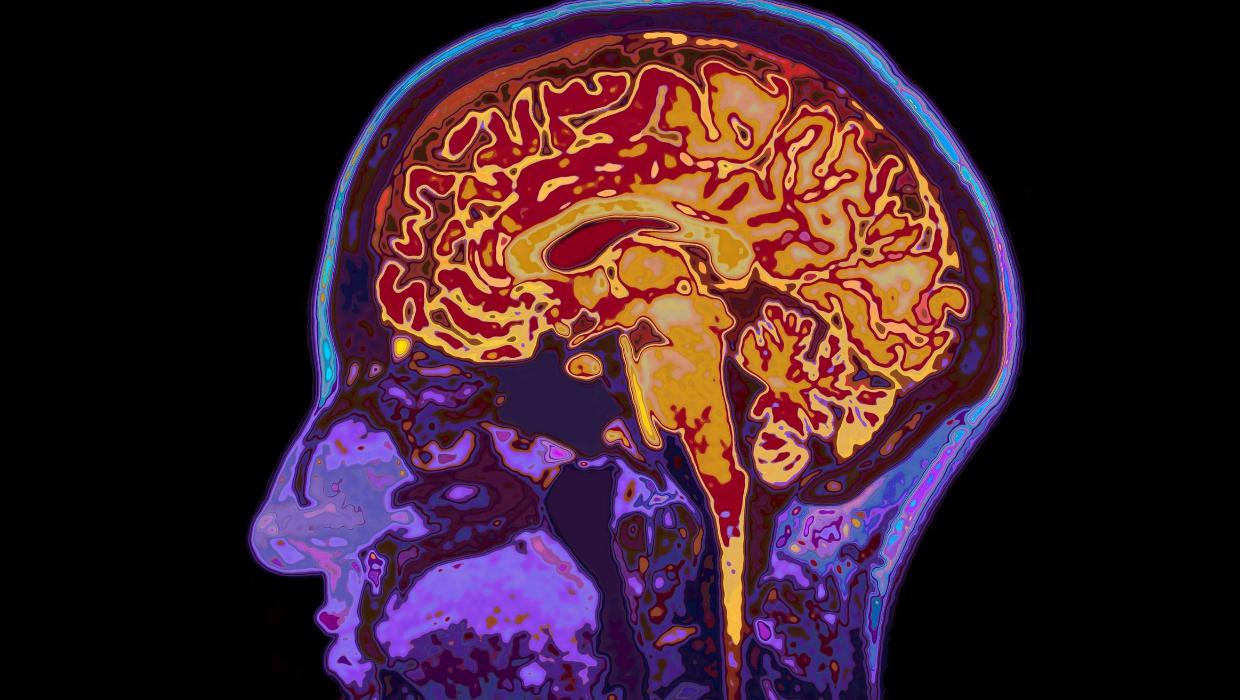

A recent study conducted by the University of Cambridge has revealed that human brain development continues into the early thirties, with significant changes occurring at various stages throughout life. The research identifies five major epochs of brain maturation, highlighting four critical turning points that shape cognitive abilities and emotional regulation.

The study indicates that the brain remains in a state of adolescence until around the age of 32. This finding challenges the traditional view that brain development concludes in the late teens. Instead, it suggests that the brain undergoes substantial maturation well into adulthood, influencing decision-making and social interactions.

Researchers have outlined four pivotal phases in brain development. The first stage, known as the early childhood epoch, focuses on the rapid growth of brain connections. This period is followed by a second phase in late childhood and early adolescence, where cognitive functions begin to mature, allowing for more complex thinking.

The third epoch, which extends into the mid-twenties, sees the brain refining its neural networks. The final phase, beginning in the late twenties and continuing until age 32, is characterized by enhanced emotional regulation and decision-making capabilities.

Interestingly, the study also notes that the process of aging in the brain typically starts around 66 years of age. This shift marks a decline in cognitive functions that can affect memory, reasoning, and overall mental health. Understanding these developmental phases is crucial as it underscores the importance of lifelong learning and mental engagement.